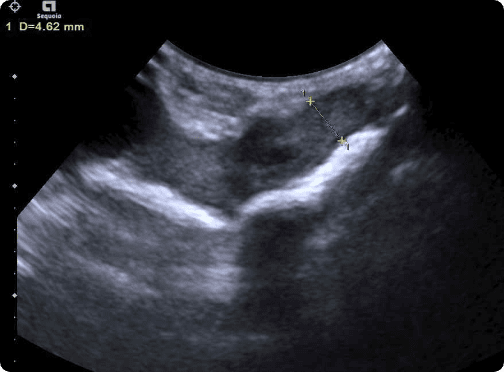

피부질환, wet tail 같은 소화기 문제의 내과질환부터

햄스터 자궁축농증 수술, 종괴제거 수술, 알막힘 등 다양한 질환을 치료합니다.